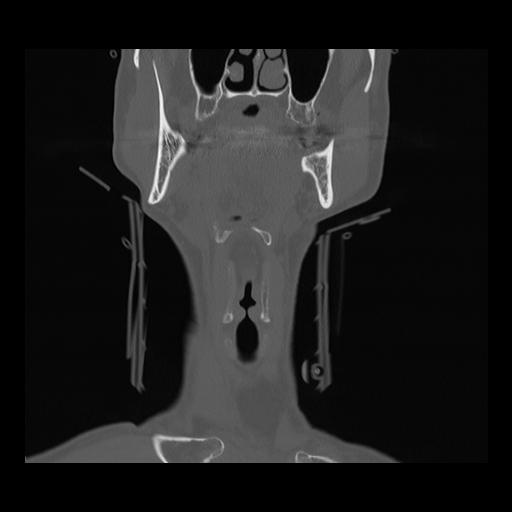

16 HUESO,,Coronal,2.000,HUESO,Coronal,